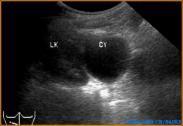

腎囊腫

• 腎囊腫

628健康網為您分享有關腎囊腫的癥狀,腎囊腫的治療方法,腎囊腫的預防知識,腎囊腫的癥狀圖片,腎囊腫吃什么藥,腎囊腫怎么治...